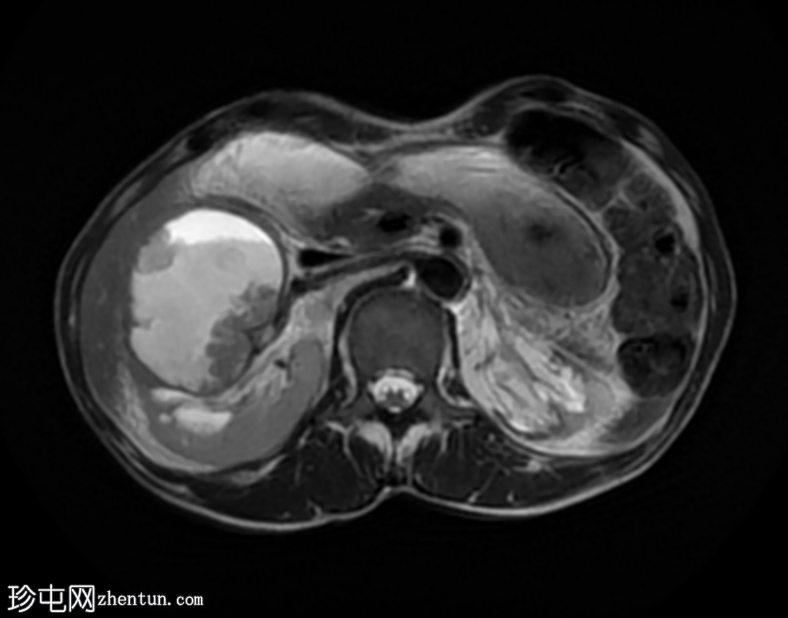

轴位

T2加权像

再次观察到上述肾前部外生性病变,其实性成分在T1加权像上呈等高信号,在T2加权像上呈低信号,伴有碎片扩散受限和低ADC值(化脓性物质)。囊性成分内部可见液-碎片/脓液界面。可见内部低信号结石。可见肾周模糊影。该病变压迫并可能侵犯右肾盂,导致中度肾积水。

病灶不规则的低信号,以及液-液界面伴有碎屑(可能为化脓性物质)扩散受限和肾周模糊,再次高度提示炎症性病变(黄色肉芽肿性肾盂肾炎,XGP),而非可能性较小的肿瘤。